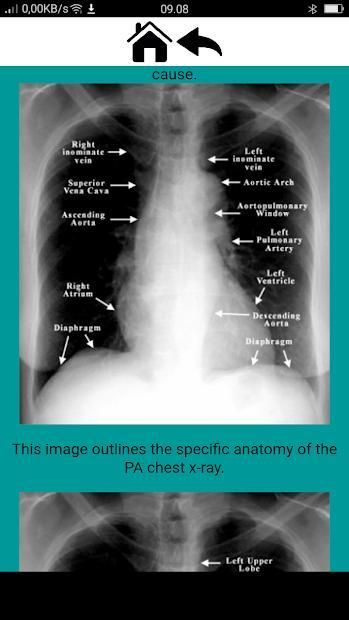

> Anatomy